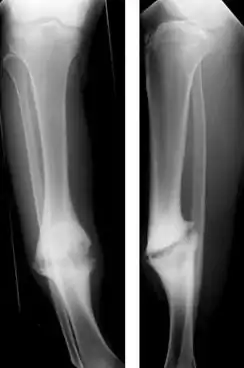

Hypertrophic nonunion of the tibia | |

Hypertrophic nonunion

In a hypertrophic nonunion, the fracture site contains adequate blood supply but the fracture ends fail to heal together.[6] X-rays show abundant callus formation. This type of nonunion is thought to occur when the body has adequate biology, such as stem cells and blood supply, but inadequate stability, meaning the bone ends are moving too much. Typically, the treatment consists of increasing stability of the fracture site with surgical implants.[7]